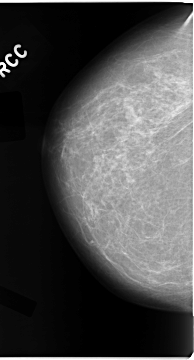

C_0047_1.RIGHT_CC

RIGHT_CC LINES 4680 PIXELS_PER_LINE 2512 BITS_PER_PIXEL 12 RESOLUTION 50 NON_OVERLAY